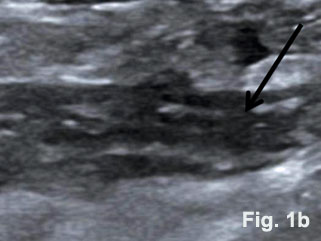

A 34-year-old complained about a sudden onset of right-lower-quadrant pain. Preoperative ultrasound revealed the appendix with a hypoechoic and thickened wall and the so-called dome sign [Figure 1]. Abdominal tenderness and other clinical signs were suggestive of acute appendicitis. On clinical examination tachycardia (108/min), febrile temperature (38.60 C) and dehydration were documented. Blood test results showed leucocytosis (13,2/nl). Emergency laparoscopic appendecectomy was performed. A large inflammatory mass was found involving the appendix [Figure 2]. The histological specimen revealed the combined presentation of congenital and acquired diverticula. Histopathological examination confirmed phlegmonous inflammation of the appendix and periappendicitis caused by inflammation of diverticula [Figure 3].

Here we present the sonographic findings of a diverticulitis of the appendix including histology. The diverticulum could be clearly displayed in an otherwise thickened appendix with well preserved layers. Diverticula of the appendix can be true or congenital or false (due to acquired mechanisms) [Table 1 and 2] [(1)]. The wall of congenital diverticula contains all the normal histological components of the appendiceal wall. The walls of the acquired or false appendiceal diverticulum are only composed of mucosa, some loose areolar tissue and the serosa. This group either develops during the growth of the fetus or before inflammatory changes make there appearence in the appendix. The prevalence of congenital diverticula found in appendicectomy specimens range from 0,004 % to 0,6 % [(2)]. Diverticulitis of diverticula of the appendix is even rarer. Approximately 78% of cases were associated with varying signs and degrees of inflammation at time of their removal [(3)]. Perforation was observed in 66 % of cases with a high mortality (30-fold compared with acute appendicitis). Four subtypes of appendicular diverticulosis have been described in the literature [Table 2] [(1)]. The majority of diverticula of the appendix described in the literature were incidental findings observed during routine X ray examination of the gastrointestinal tract. While it is agreed that many people with appendiceal diverticula live healthy, normal lives, there can be no doubt that with the onset of complications, life is threatened by inflammation and complications.